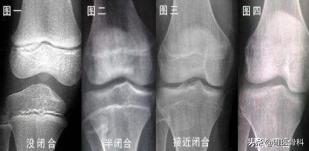

什么是骨骺线?骨骺线就是骨骺与干骺端之间的软骨,在X光片上表现为一条较宽的透光带,它随着年龄的增长而逐渐变短。

青春期发育过后,骨骺线就开始变得模糊,最后形成一条严密的缝,意味着骨骺线快闭合了,骨头不会长了,但这并不意味着不能继续长高,因为人的脊椎闭合的时间要比四肢晚,即使四肢的骨骺线闭合了,脊椎还是有生长空间的,大概会生长到23-26岁。所以,人们常说”23,蹿一蹿“,还是有一定道理的。这就是我们为什么会惊讶NBA里如火如荼的190cm的林书豪,刚上大学时也只有不到180cm。